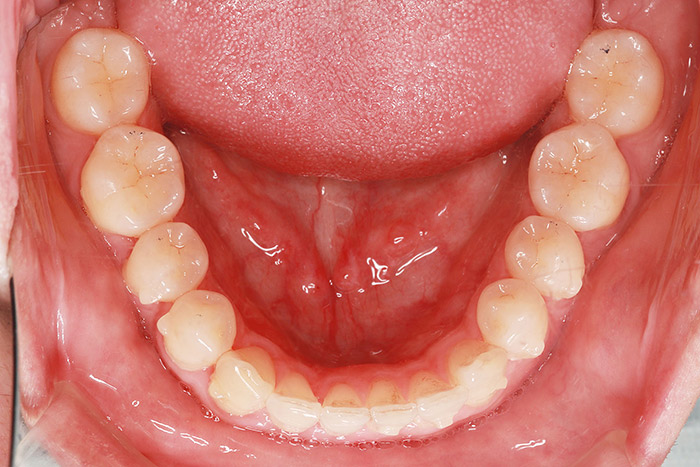

K様

治療後

年齢 27歳

性別 女性

治療名称 マウスピース型カスタムメイド矯正歯科装置(インビザライン)・コンプリヘンシブパッケージ(フルパッケージ)

総額治療費用 770,000円(税込10%) 金額備考 精密検査料・診断料 33,000円(税込10%)

治療期間 1年11か月 通院頻度など 40日ごと

1枚につき10日装着を指示しました。

治療内容

患者の症状 上顎前歯の前突、八重歯

治療方法 上下左右の第一小臼歯抜歯で、マウスピース型カスタムメイド矯正歯科装置による矯正

治療結果 上顎前歯の前突、八重歯が改善されました。

歯並びをより良くするために追加でアライナーを発注しました。

リスク/副作用 決められた時間装着する必要があります。